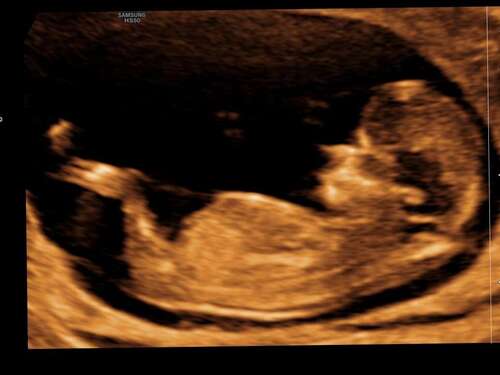

Wat denken jullie 💙🩷

Wat denken jullie? 12 weken💗💙

💕 meisje..